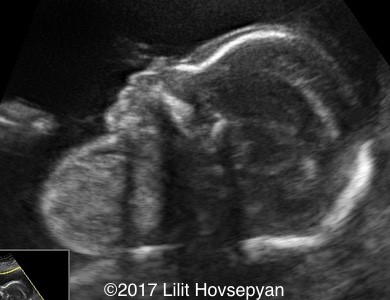

Cleft Lip & Cervical Teratoma

CLEFT LIP

Ass with: polyhydramnios, hypertelorism, micrognathia